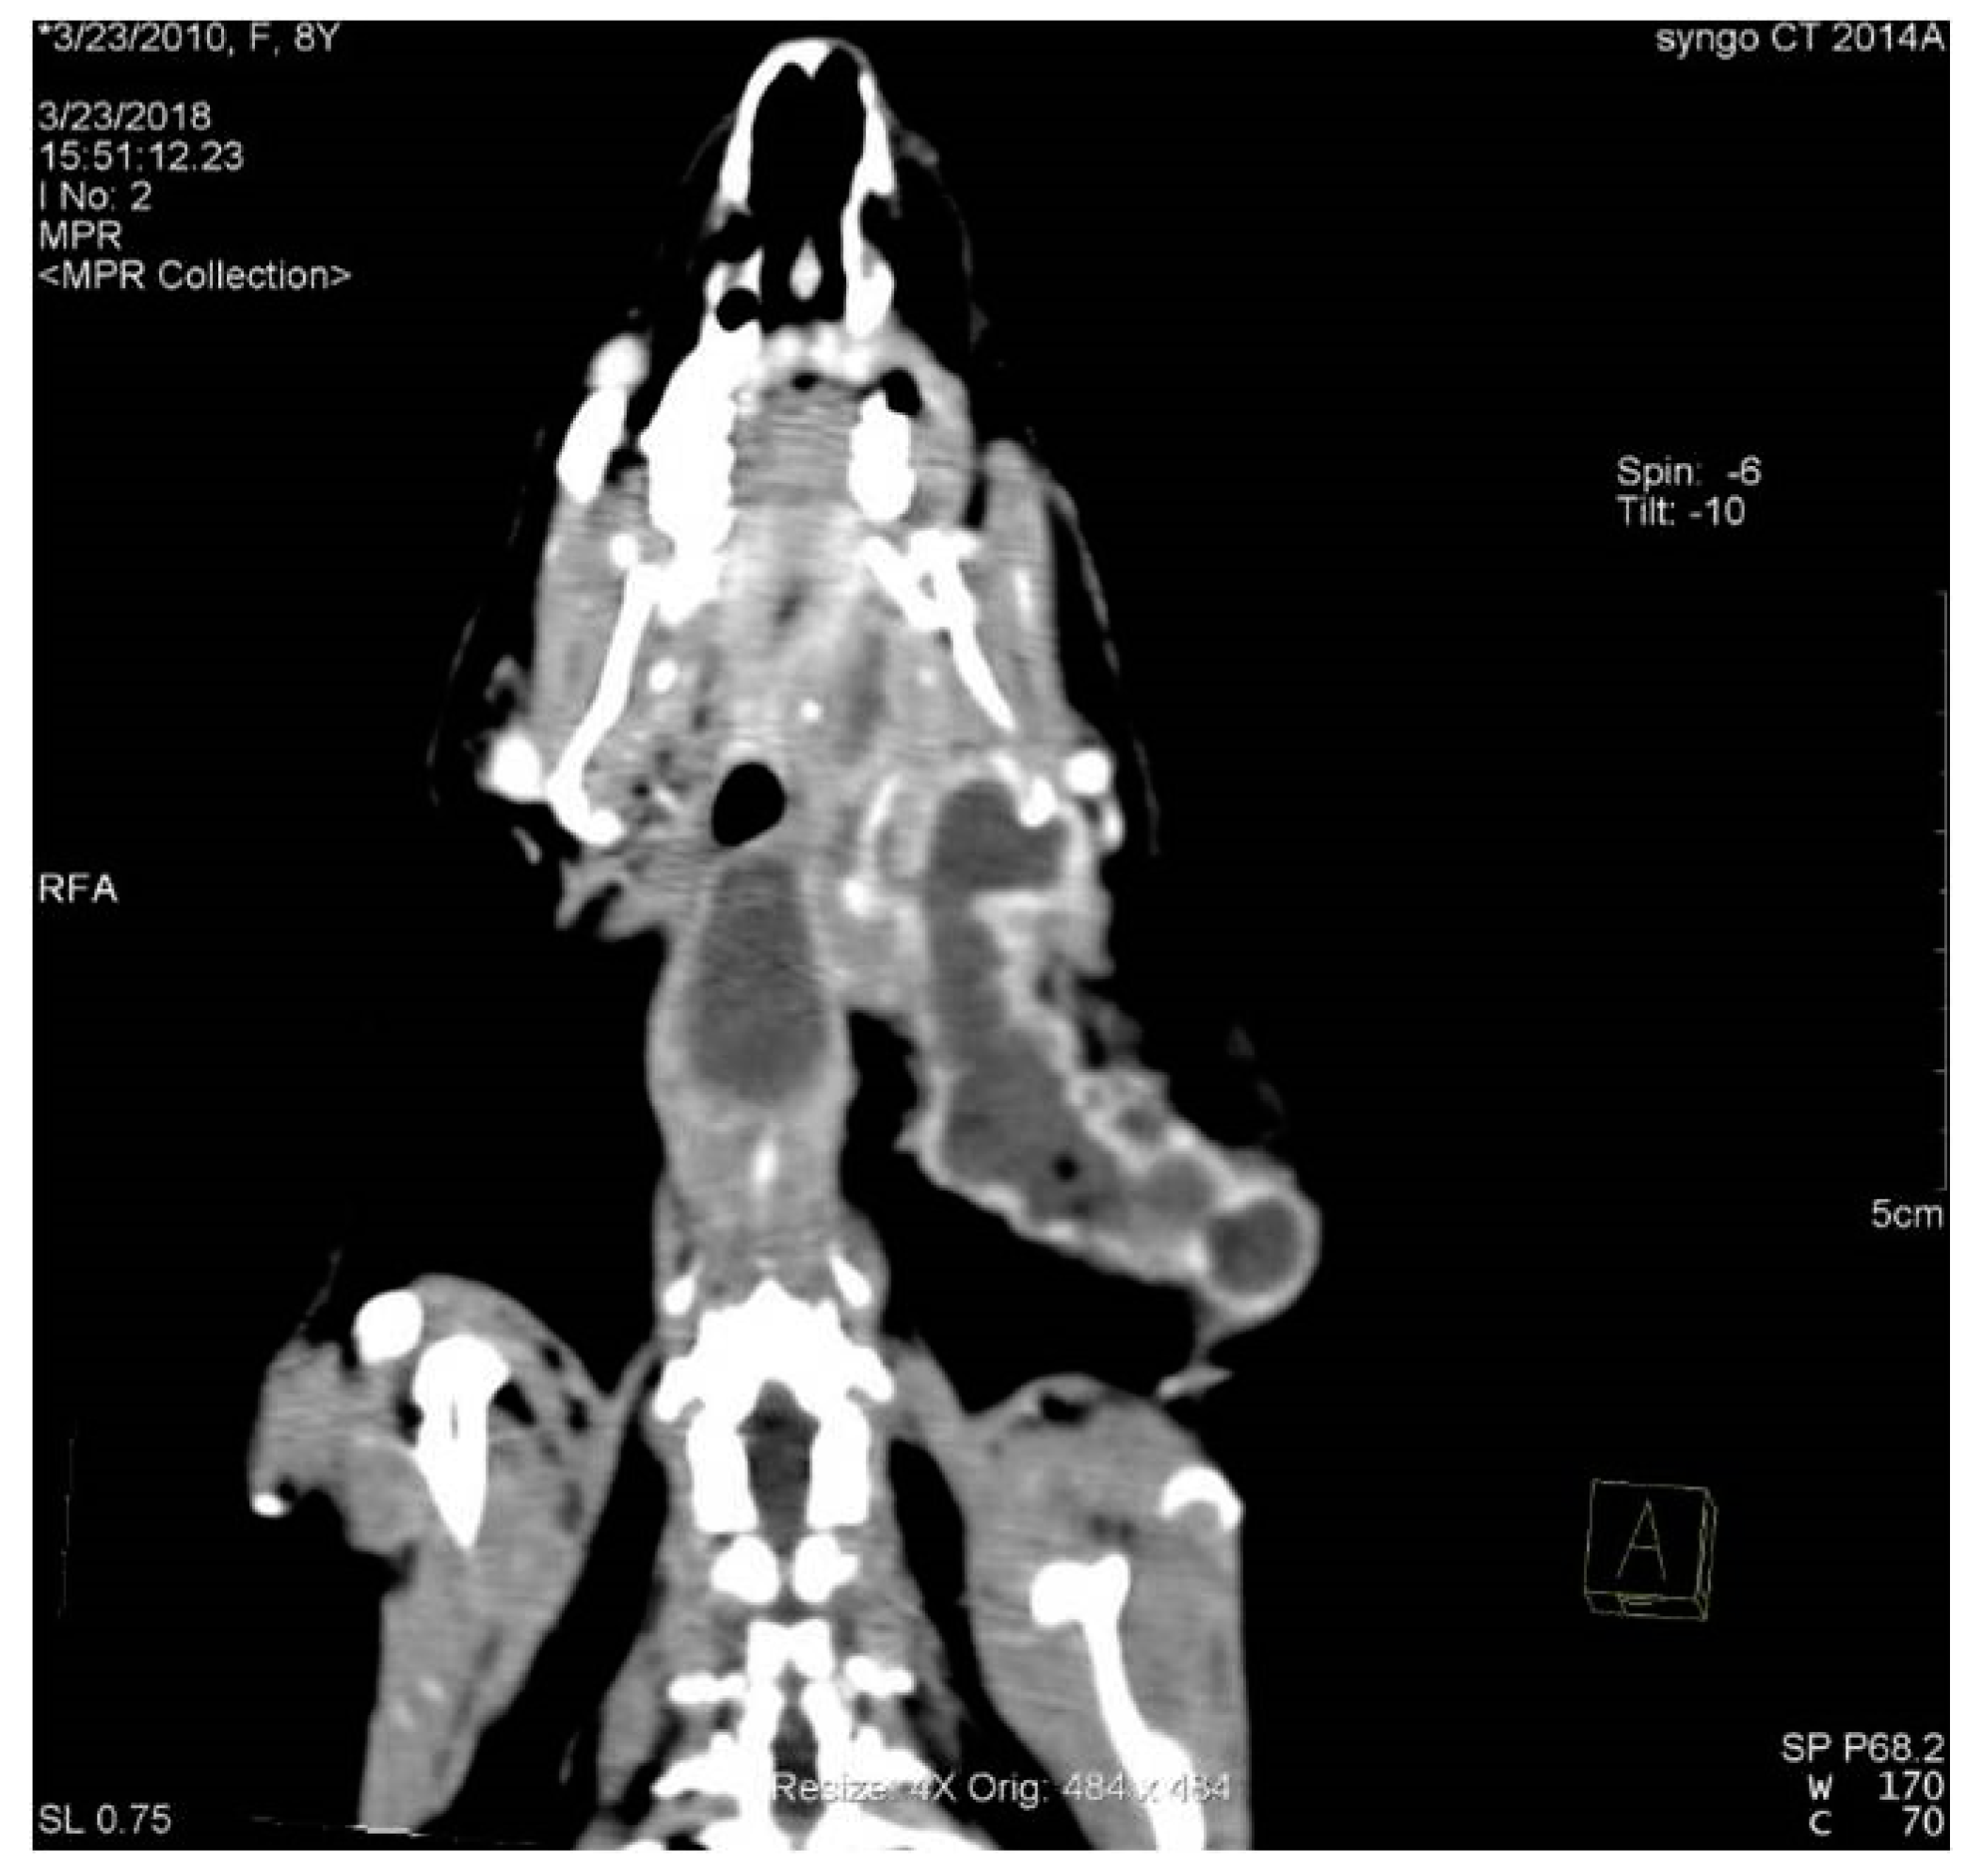

3.5. Incidence of Dental Abscesses and Secondary Osteomyelitis